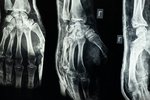

Je použitie radiofarmaka pri gamagrafii skeletu bezpečné?

Zdravotníci prosím Vás o názor...je použitie radiofarmaka bezpečné? Keď laik počuje že chcú do neho pichnúť rádioaktívnu látku znie to dosť nebezpečne 😄 ďakujem. Jedná sa o gamagrafiu skeletu.